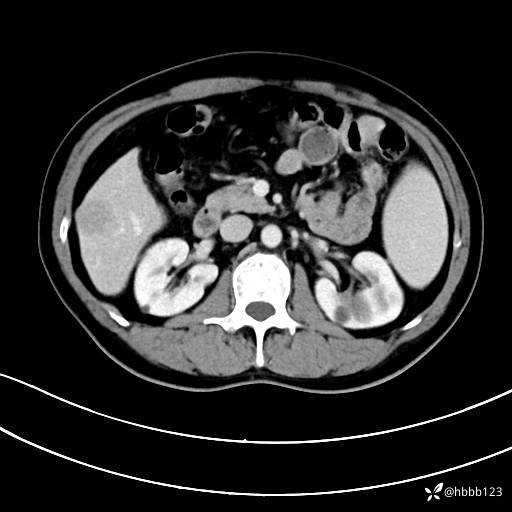

动脉期: